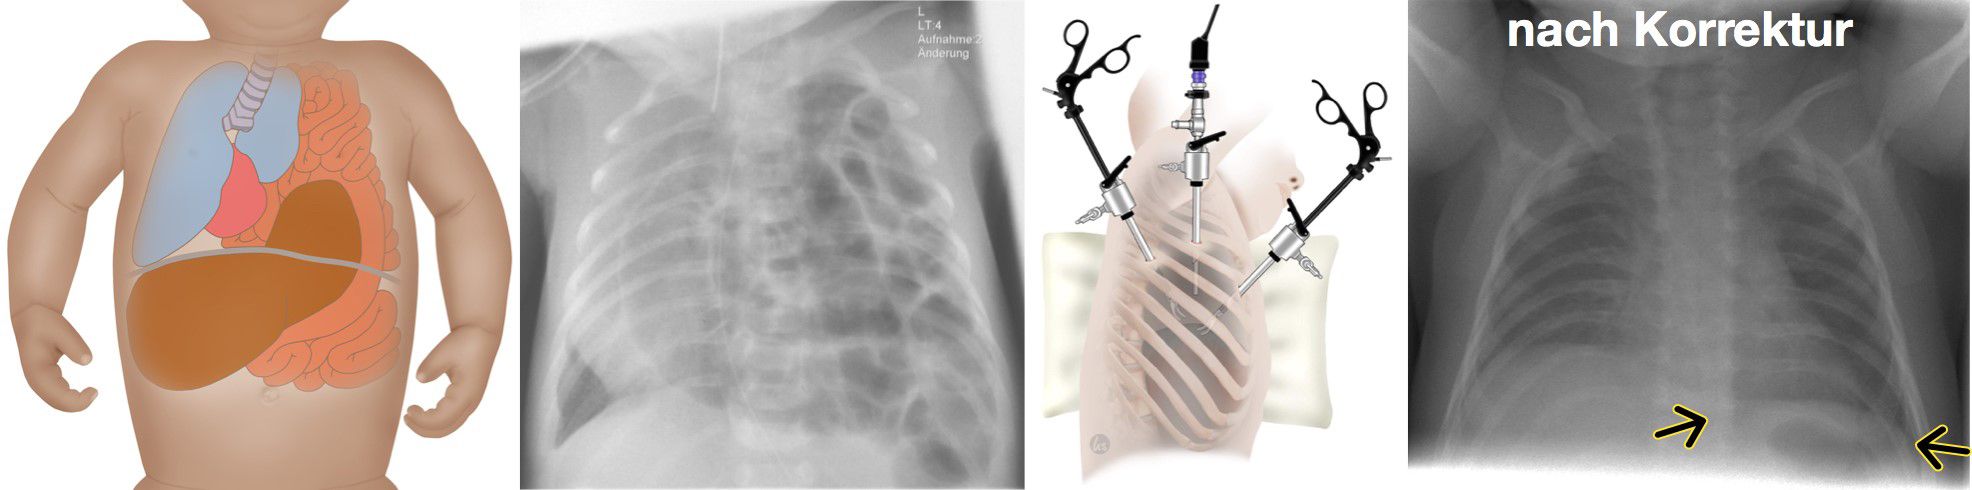

Zwerchfellhernien sind angeborene Defekte des Zwerchfells. Diese werden bei den meisten Kindern vor Geburt im Ultraschall erkannt. Je nach Lokalisation und Ausprägung verursachen sie teilweise erhebliche Probleme mit der Atmung für das Neugeborene. Deshalb sollten alle Schwangeren bei deren Kindern diese Fehlbildung festgestellt wird eng an ein Zentrum wie Tübingen angebunden werden und das Kind dort zur Welt bringen. bereits vor Geburt  Bereits in der Diagnostik vor Geburt mit Ultraschall und Kernspintomographie lässt sich das Risiko für die Beeinträchtigung der Atmung anhand der Lungengröße abschätzen. Damit ist gewährleistet, dass die Geburtshelfer, die Neonatologen und Kinderintensivmediziner darauf vorbereitet sind und alle Therapiemöglichkeiten direkt zur Verfügung stehen. Dies umfasst am Universitätsklinikum Tübingen alle modernen Therapieoptionen beginnend von Eingriffen im Mutterleib, über eine direkte Versorgung des Neugeborenen solange es noch durch die Nabelschnur versorgt wird bis hin zu speziellen Beatmungsformen nach Geburt und der Sauerstoffzufuhr über das Blut (ECMO). Als überregionales Zentrum für Fehlbildungen beim Neugeborenen sind alle diese Therapieformen bei uns mit jahrelanger Erfahrung etabliert.

Nach Geburt wird das Kind zunächst über mehrere Tage hinweg intensivmedizinisch stabilisiert, bis eine Operation möglich ist. Nach entsprechender Patientenselektion wird die Korrektur minimalinvasiv oder offen chirurgisch durchgeführt.

In jeder Phase der Behandlung ist gewährleistet, dass optimale Therapie interdisziplinär hochkompetent von Spezialisten durchgeführt wird.

Zwerchfellhernie: Abb. links nach Korrektur.

Zwerchfellhernie: Abb. rechts nach Korrektur.